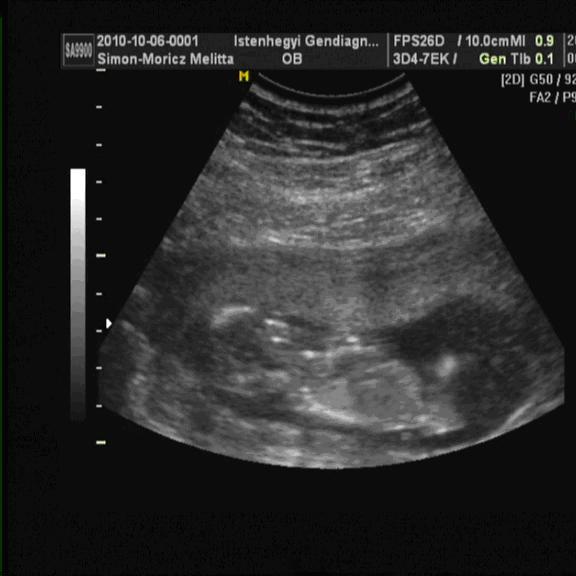

Akkor végre a két magzatunk sorrendben.

Kép A baba

Kép B baba

momelcsi

Melcsi, húúú nagyon cukik és milyen jól látszanak :lol: 4Ds ultrahangra is mentek majd? Neveitek már vannak vagy csak akkor döntitek el,ha megtudjátok a nemüket?